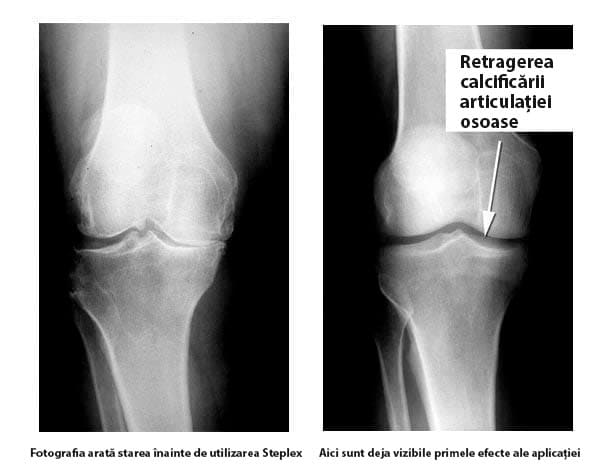

Reconstrucția articulației atrofiate a genunchiului. Persoana a folosit Hondro Sol spray în fiecare zi timp de o lună. Structura articulației și mobilitatea acesteia sunt complet restaurate. Nu există durere.